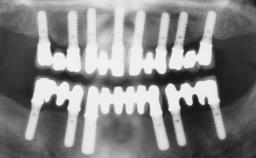

# of Implants 6

Defining Characteristics Fully edentulous upper jaw to be rehabilitated with four or more implants

Modality 6+ implants with immediate loading